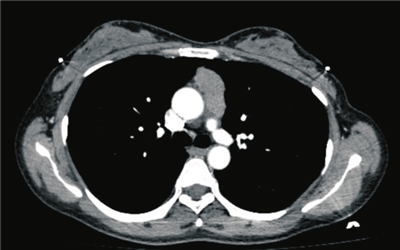

近日,一名患有纵隔肿物的患者来院就诊,胸外科负责人、第一胸外科病房主任赵俊刚团队进行了充分的术前讨论,决定应用达芬奇手术机器人为患者进行经剑突下纵隔肿物切除。

与传统胸腔镜纵隔肿物切除手术不同,经剑突下纵隔肿物切除术采用剑突下单切口联合双侧锁中线与肋弓下缘交点处辅助切口进行操作,不经过肋床,完整保留胸壁结构,术后患者无肋间神经痛,康复快、住院周期短。机器人手术有着可以充分暴露纵隔内复杂组织结构,视野更开阔的特点,在切除胸腺、心包前及膈肌上方脂肪组织方面能更好的达到根治性手术的标准。手术当天,赵俊刚在操作台通过控制三个机械臂进行精细操作,仅历时1小时便成功完整切除了纵隔肿物。患者现已康复出院。